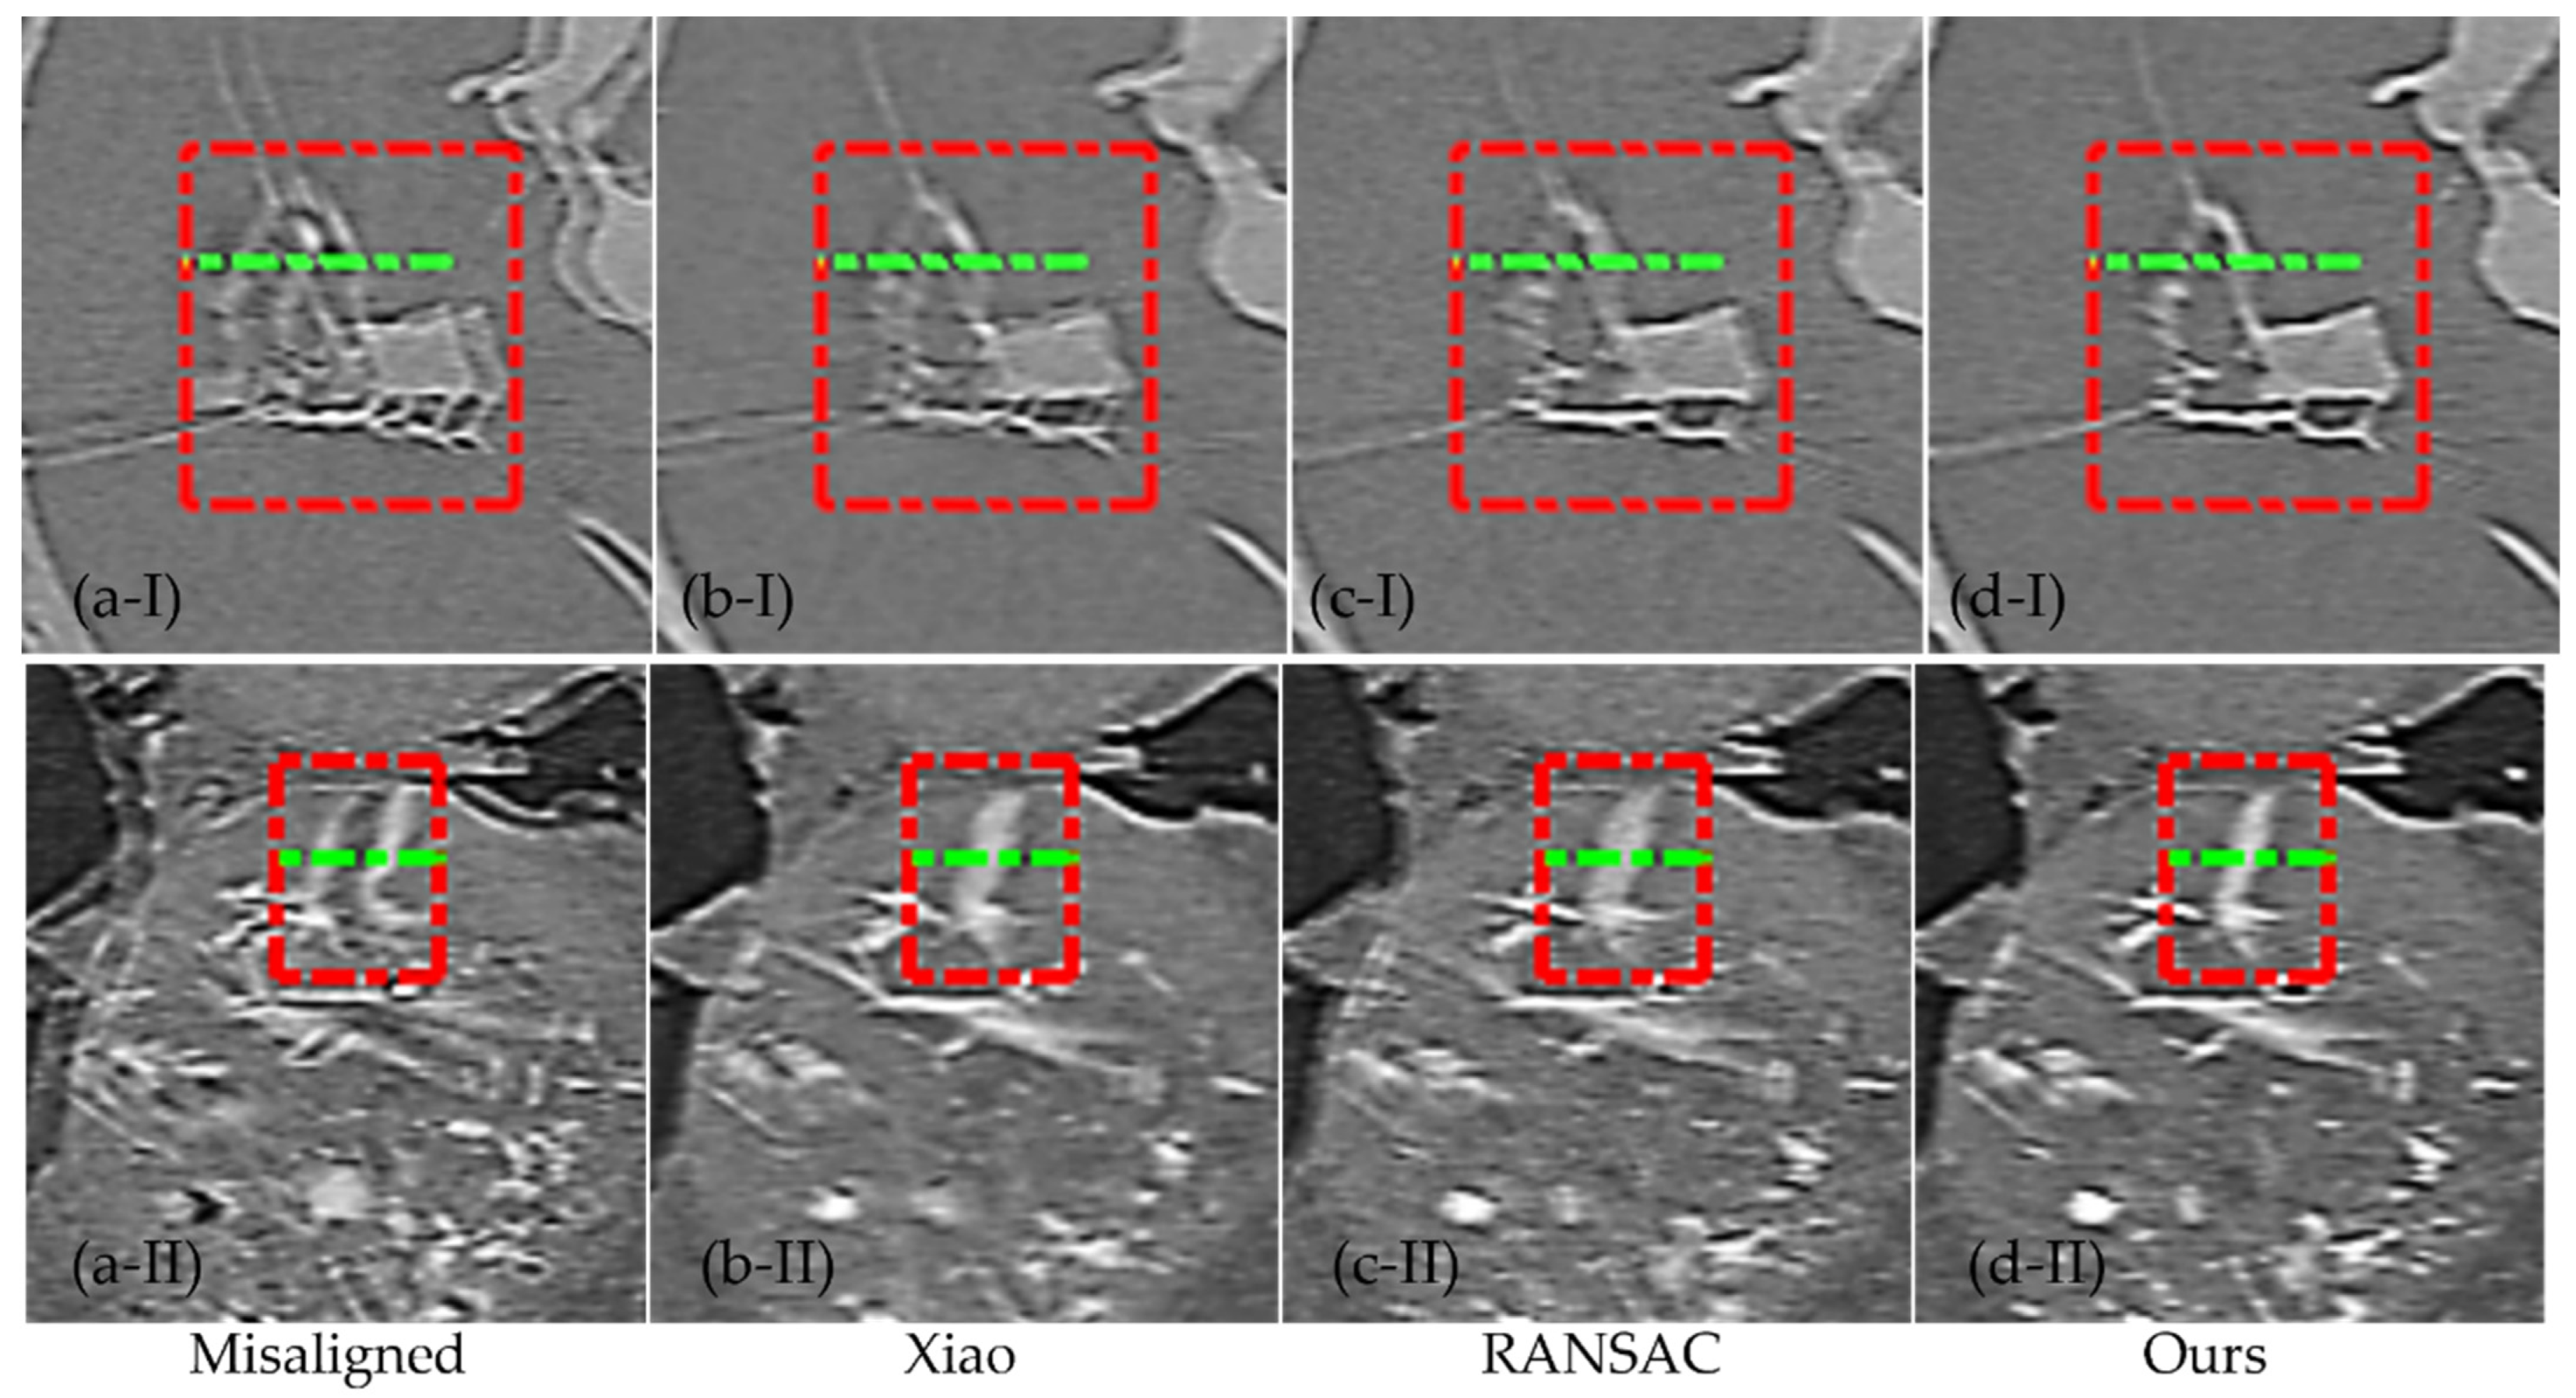

3.2. Nanotomography Experimental Section